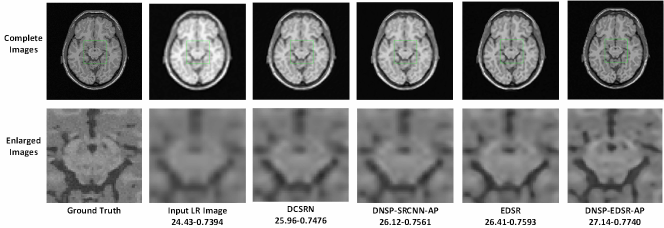

Figure 11: Comparisons of top 4 methods for an image in BW data set for scale factor of 2. A small portion of the images (marked by green box) in the first row is zoomed in and shown in second row. The numerical figures constitute the respective PSNR-SSIM values.

Table II shows PSNR and SSIM values for all competing methods. Note that we used two different base networks for DNSP: 1) DNSP-SRCNN-AP - the base network is SRCNN and 2) DNSP-EDSR-AP - the base network is EDSR. Three trends emerge from the results: 1) DNSP-EDSR-AP outperforms the competition, 2) DNSP-SRCNN-AP does better than all the methods except EDSR, and 3) overall, deep SR methods, i.e. SRCNN, EDSR, DCSRN and DNSP perform better than other alternatives. To confirm this statistically, we performed a 2-way Analysis of Variance (ANOVA) on PSNR values for all the methods across the two datasets which is illustrated in Fig. 10. It may be inferred from Fig. 10 that deep learning methods are statistically well separated from the traditional methods and further DNSP-EDSR-AP is well separated from all the competing methods indicating the effectiveness of using prior information. Figures 11 and 12 illustrate the results of the top 4 methods w.r.t. PSNR on a sample image from BW and ADNI databases respectively for a down-sampling factor of 2 while Figures 13 and 14 show results for a down-sampling factor of 4. DNSP-EDSR-AP particularly excels in recovering fine image detail (enlarged with zoom-in boxes), thanks to data-adaptive sharpness.